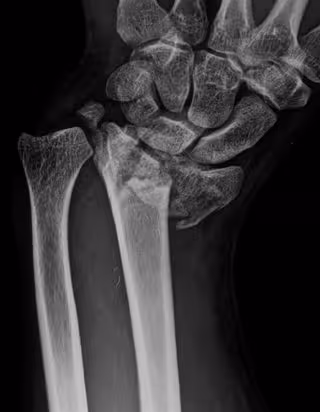

Experto avisa de que se están diagnosticando y tratando inadecuadamente las fracturas de radio

Fractura de radio